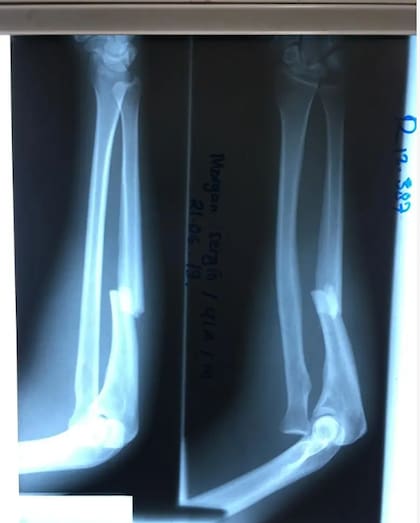

“Vi como el aire, la pared, las piedras me pasaban lentamente. Y pensé que tenía que aferrarme a algo para detenerme, pero lo único que tenía disponible era la piedra. Así que intenté agarrarla con toda mis fuerzas, pero todos mis dedos se rompieron”.

Luego de caer casi 40 metros, Segui se golpeó en la cabeza y quedó inconsciente durante al menos tres horas.

Cuando Morgan Segui recobró del todo la consciencia, concluyó que se iba a morir. De su cabeza colgaba parte de su cuero cabelludo, sus dedos estaban rotos y no podía mover el brazo derecho.

Al día siguiente, Segui usó todas sus fuerzas para incorporarse, a pesar de tener fracturas en su pie derecho y en varias otras partes del cuerpo. Usó su camiseta para inmovilizar su brazo fracturado y se dirigió al camino que había visto a las cabras usar.